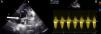

A 21-year-old woman was admitted to our clinic with dyspnea. Her medical history was unremarkable. Right bundle branch block was identified on 12-lead ECG and mediastinal enlargement on the chest X-ray. Transthoracic and transesophageal echocardiographic examination showed a lobulated cystic image in the left atrium and secundum-type atrial septal defect (Figures 1 and 2). Additionally, in short-axis view a mass was visualized invading the pulmonary artery, and continuous wave Doppler of the pulmonary artery revealed a maximum gradient of 40 mmHg. A detailed examination with cardiac magnetic resonance imaging demonstrated a multicystic mass in the mediastinum compressing the main pulmonary artery, predominantly the left branch (Figure 3). The patient was diagnosed with secundum atrial septal defect and mediastinal hydatid cyst on the basis of serologic tests and detailed history. Surgical therapy was offered and she asked for time to think. Medication with albendazole was started, but she was then lost to follow-up.